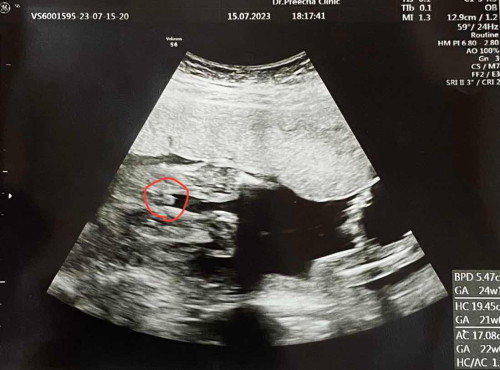

ดูน้ำหนักลูกตรงไหนคะในผลอัลตราซาวน์

อยากทราบว่าดูน้ำหนักน้องตรงไหนในใบรายงานผลอัลตราซาวน์คะ คุณเเม่